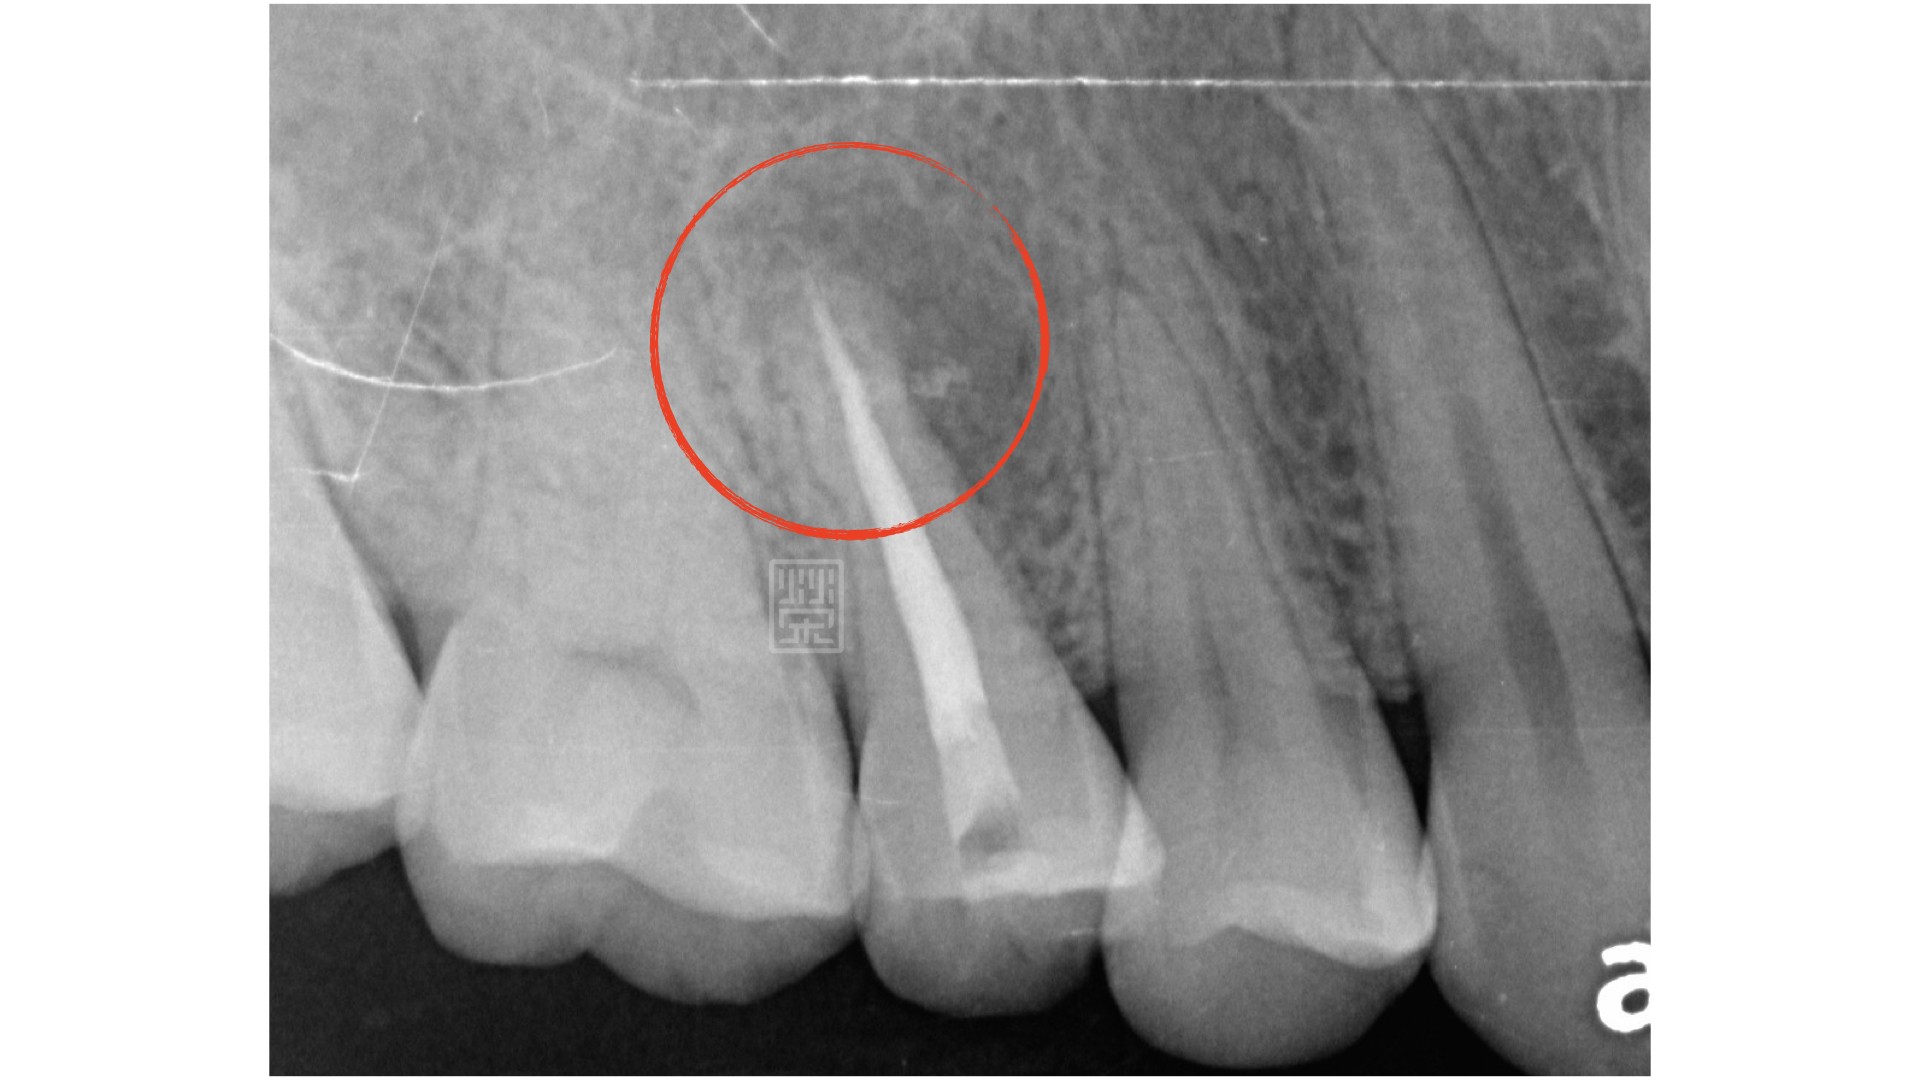

小臼齒牙根尖處,有部分未充填,並且牙根尖周圍有骨頭受傷的跡象。

陳小姐四年前來診就診處理門牙問題,當時有檢查到小臼齒在根尖處有部分沒有填充,並且牙根尖周圍處有骨頭受傷的跡象,但當時沒不舒服並且已經治療完多年了,所以先觀察,沒有做任何處理。

某天晚上,突然來電,描述右上小臼齒突然痛起來,而且痛到眼睛跟右邊太陽穴,回來檢查後,發現就是這顆小臼齒根尖發炎所造成,打開時還發現牙神經管腔內有發炎膿水,難怪壓力蓄積造成這麼嚴重的疼痛。重新根管治療後,將根尖的病因移除,等待牙根恢復健康,再用全瓷冠修復,恢復功能與美觀。